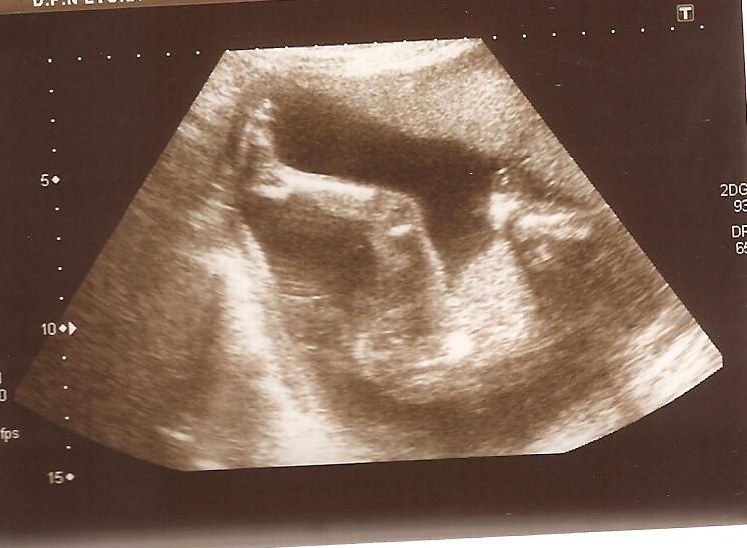

Ecografía semana 20: Bebé con labio leporino | Natalben

WebCómo detectar labio leporino en el embarazo. El diagnóstico del labio leporino se realiza tras la realización de una ecografía transvaginal. En el tercer mes de. WebCaso clinico de sindrome coronario agudo. El labio leporino suele detectarse en una ecografía a las 20 semanas de gestación, pero el paladar hendido puede ser más. WebEco-Doppler, la ecografía de las 20 semanas. En la vigésima semana de embarazo el ginecólogo te mandará una ecografía un poco especial, un Eco-Doppler.. WebLabio leporino de 3mm. Ecografía de la semana 13. En la mayoría de los casos, una ecografía prenatal puede detectar el labio leporino solo o el labio leporino y el paladar. WebLabio leporino : Hola mamis? Hoy tuve mi ecografía de 14 semanas y el doctor me dijo que puede distinguir labio leporino, pero en mi ecografía de 12 semanas. WebLos niños con labio leporino o paladar hendido pueden tener problemas para comer y respirar. Esto va a depender del tamaño de las aberturas. A medida que crecen, también. WebAsí como pueden ver si viene con síndrome de down ellos pueden ver si viene con labio leporino porque la ecografía se los indica, los médicos tienen medidas y. WebLa extensión de la ecografía de 12 semanas para el cribado del síndrome de Down y otras cromosomopatías está permitiendo la observación precoz de alteracione... WebEntre la cuarta y octava semana de embarazo, se forma la cara del bebé. En este período las partes del paladar y del labio se fusionan, y si no lo hacen, el niño tendrá labio. WebYo creo que si se ve y como dicen las compis en la eco de las 20 miran todo muy bien.De todas formas casi todas nos hacemos una eco 4d y ahi se ven los rasgos.